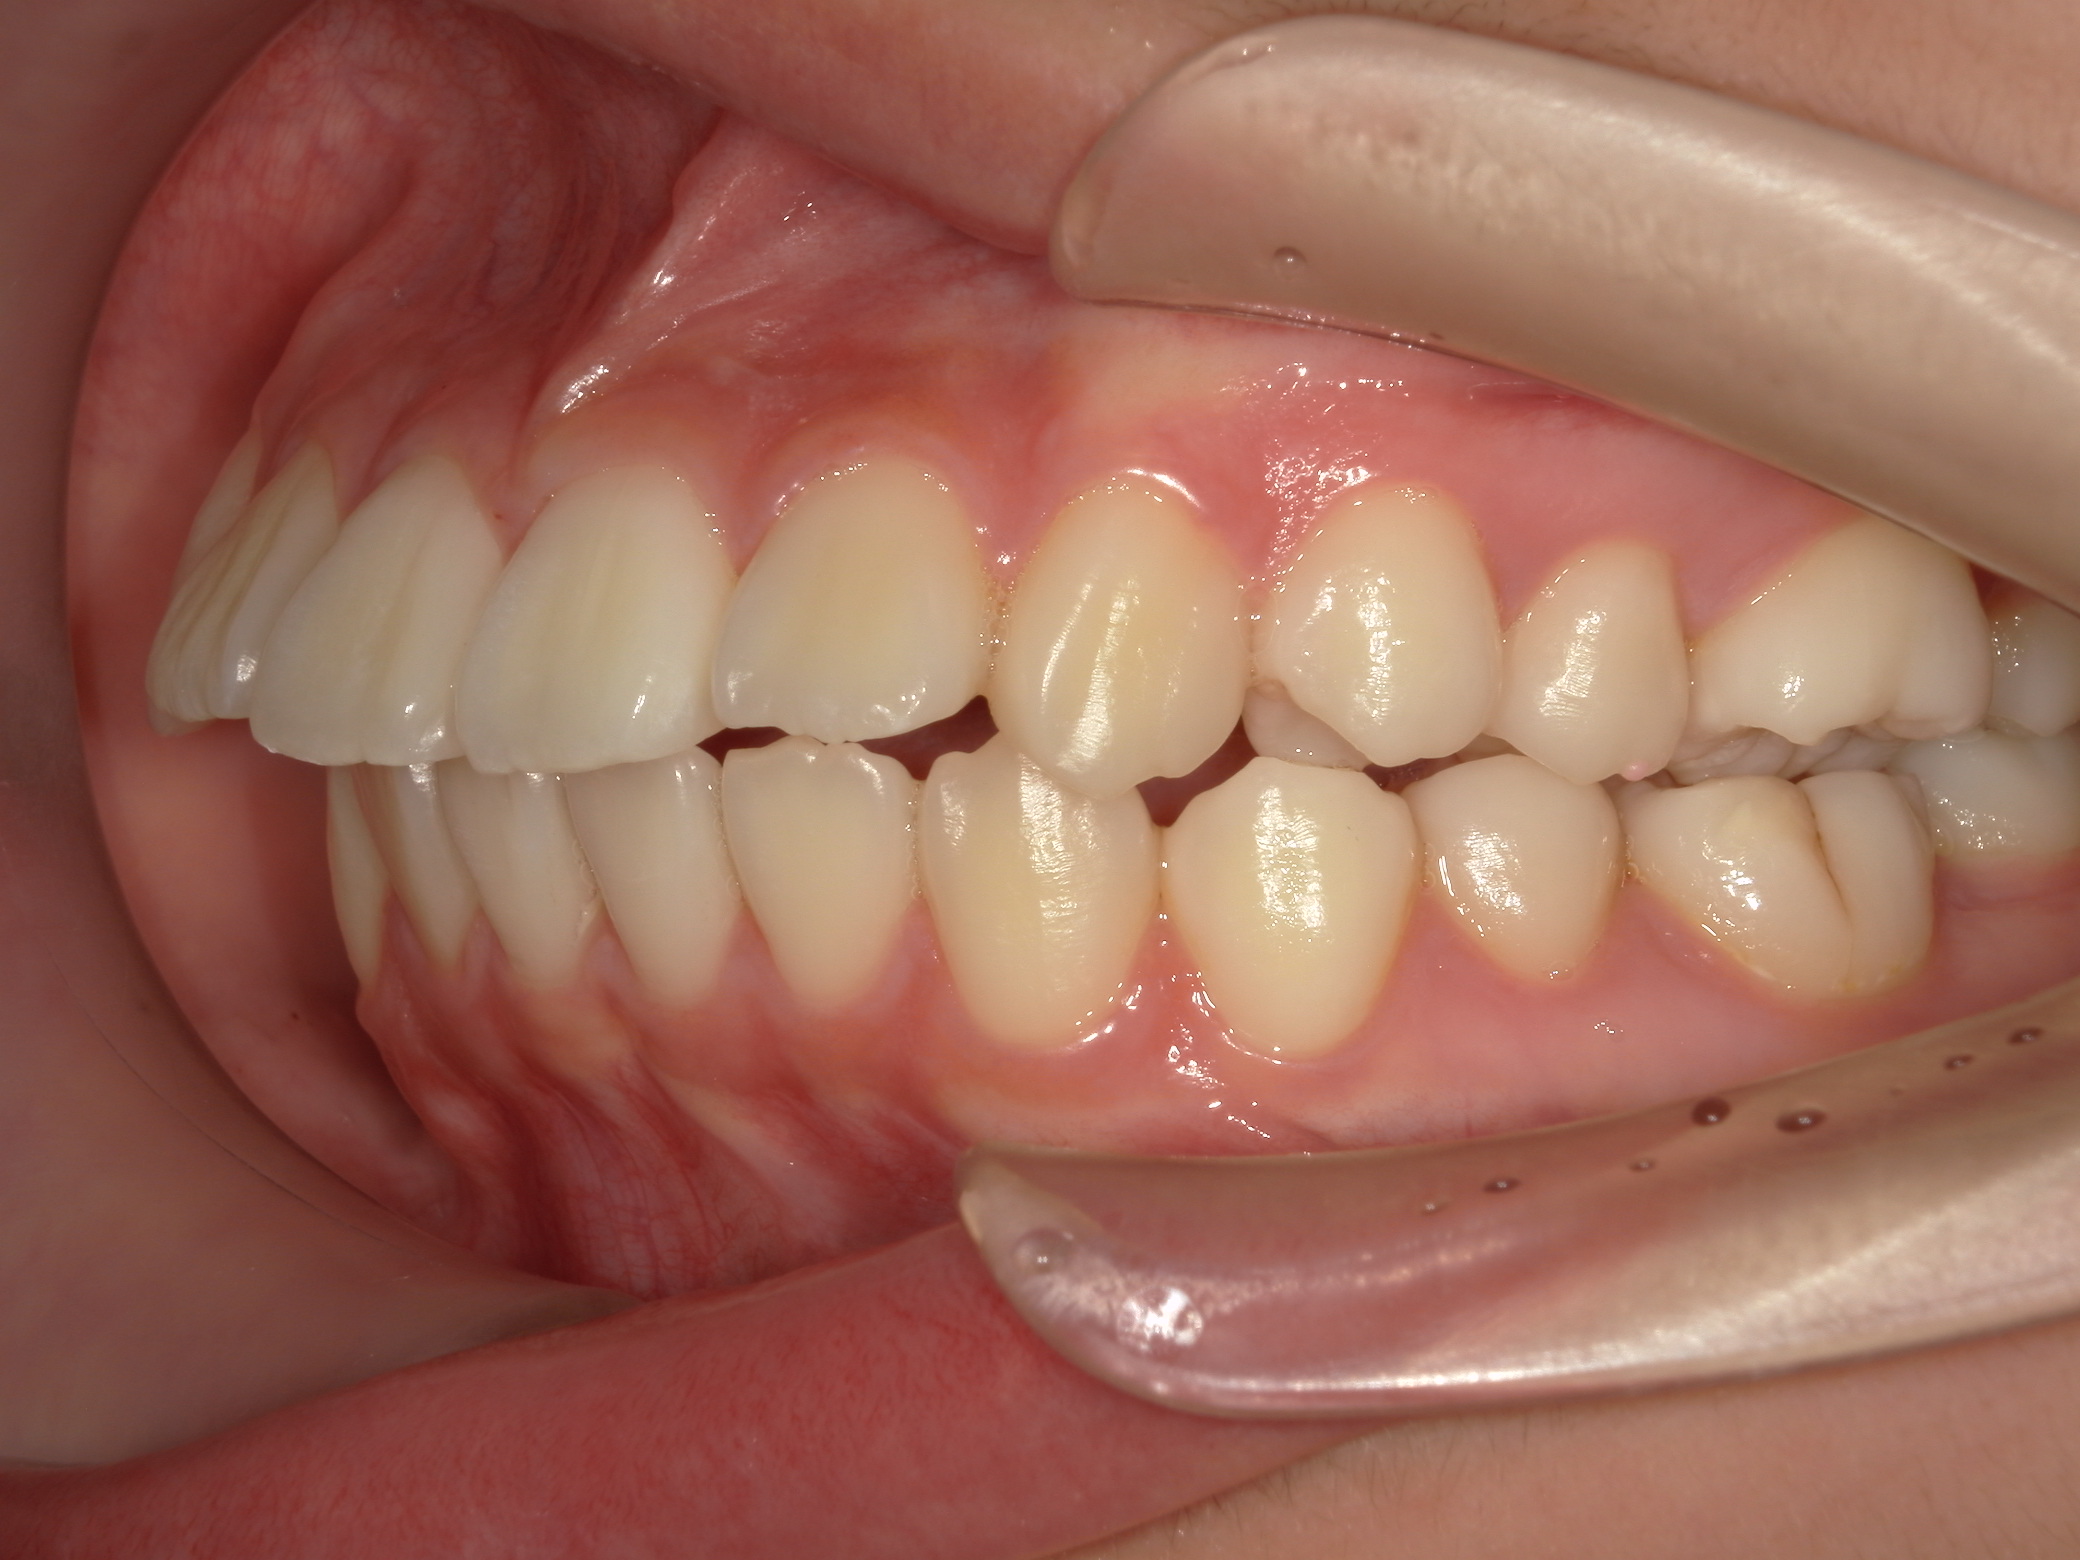

斜め横から見ると立体的に出ているのが判ります。

この症例の気になるの点として、無理な拡大で下顎左右6番の歯根が頬側の皮質骨からはみ出ている危険があることです。そうならば、下顎6番の近心移動はものすごく遅くなります。等と考えていたので、当然のごとく抜歯部位の選定に悩みました。悩んだ末、この症例は上下左右の6番抜歯症例です。

口元がすごく出ています。